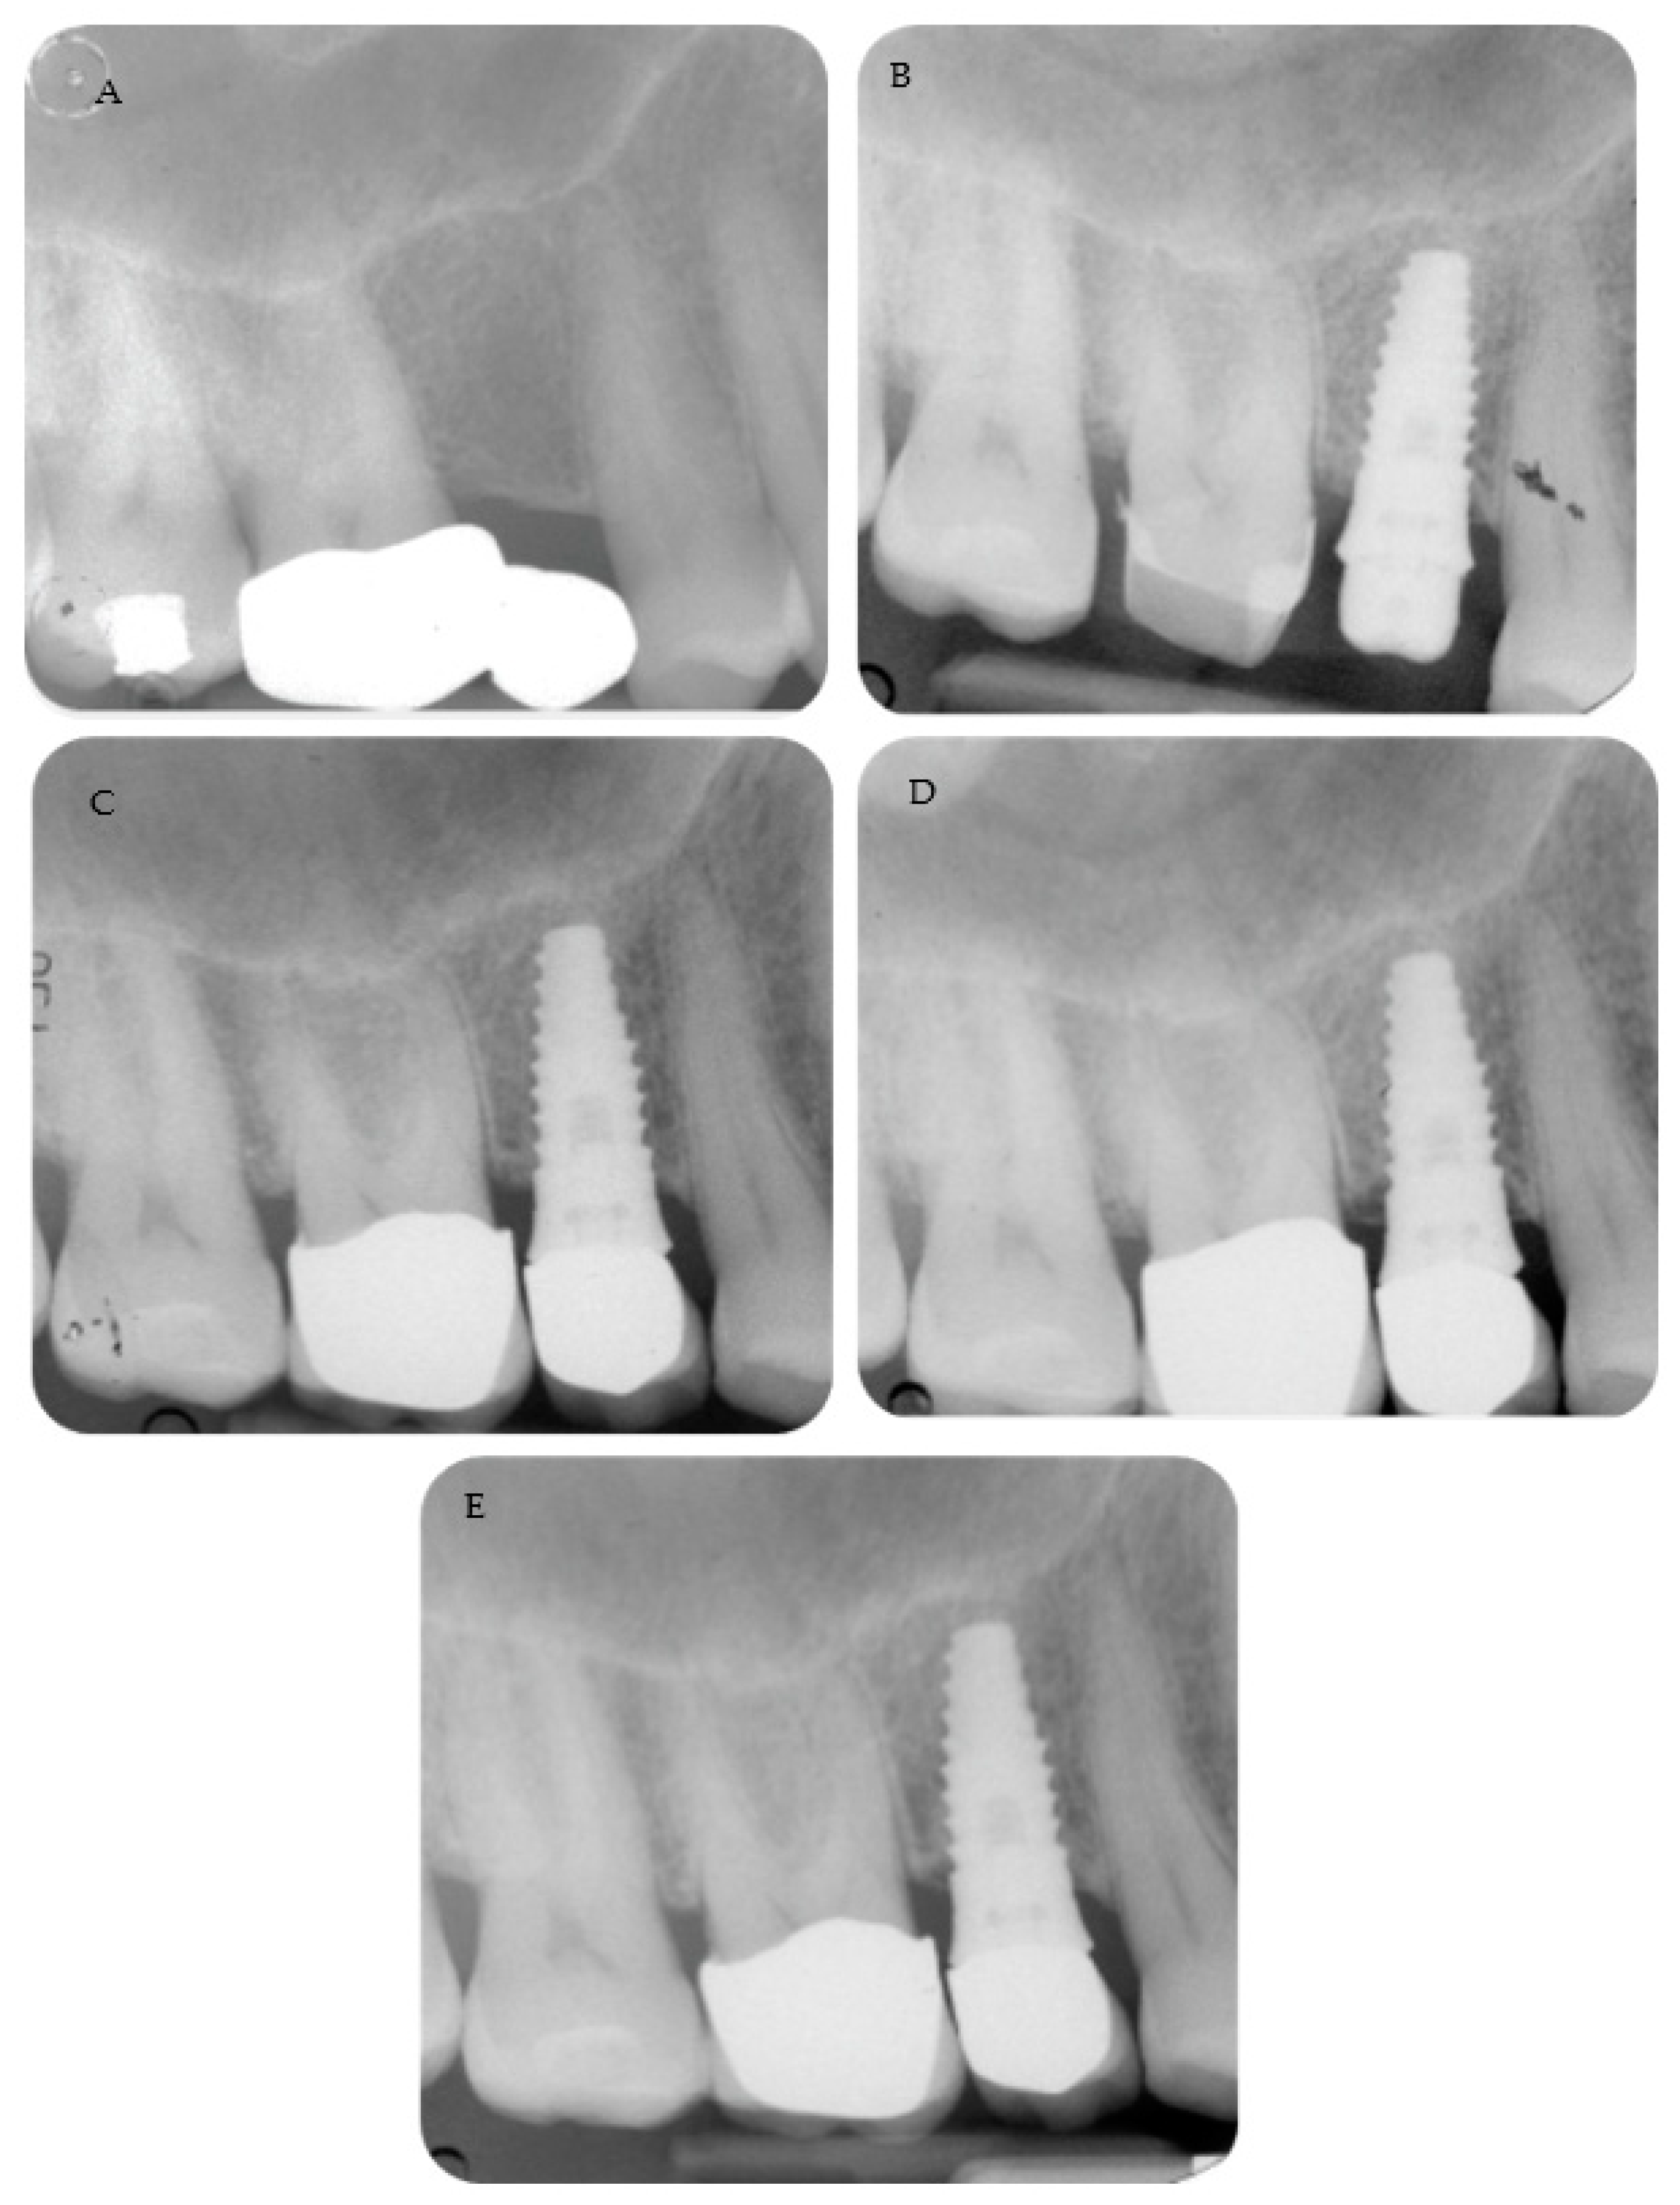

Periapical radiographs reporting two treated cases are shown in Figure 2 and Figure 3.

Figure 3. (A) Early timing placement to rehabilitate a single edentulous ridge. Tooth was extracted 2 months before for a root fracture. (B) Implant placement with a flapless approach. Please note that the neck was positioned at tissue level. (C) Periapical radiograph after abutment and definitive crown cementation. (D) Follow-up at 36 months and (E) 48 months showed MBL stability around the implant.